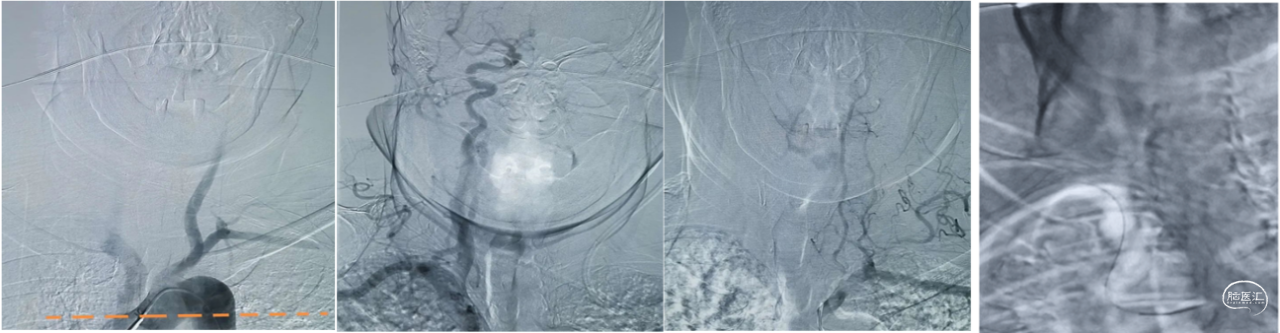

一、经桡动脉穿刺6F导引导管支撑基底动脉取栓

典型病例: 遭遇超Ⅲ型弓,经桡动脉穿刺基底动脉取栓血栓

治疗过程:患者,80岁老人,突发偏瘫、言语不能,且院内卒中,从临床表现看,应该是左侧颈内动脉系统病变。左侧颈总到位造影,未发现明显异常,但后交通较为发达,Ⅲ型弓头臂干开口太低,右侧颈总动脉到位困难,右侧颈内动脉系统无异常,但右侧椎动脉远端显影不良,左侧椎动脉发育不良,考虑基底动脉栓塞。

经股动脉入路要面对超难到位的右侧锁骨下动脉了。尝试几次都未能如愿,导引导管难以到达右侧颈总动脉导引导管,这是Ⅲ弓的难点。

手术过程

1、快速行右侧桡动脉穿刺,置于6F动脉鞘,造影管轻松到位右侧椎动脉,露出庐山真面目:基底动脉栓塞,此时,患者烦躁不安,右侧肢体肌力下降为1级,原本能活动的左侧肢体活动也开始减少,心率130次/分,病情在快速恶化。如果不能开通基底动脉,后果不堪设想。

2、0.035泥鳅导丝携带5F单弯外衬6Fguiding导引导管同轴快速到位椎动脉V2远端,撤出泥鳅导丝和单弯导管,微导丝携带Rebar-27直奔主题。必须快,而且稳,微导管找到真腔。

3、微导丝携带Rebar-27、5F Navien中间导管,微导管穿过血栓,铆定血栓打开6mm*30mm Solitaire AB支架,血流复通,一次性取出质地柔软暗红色栓塞物。